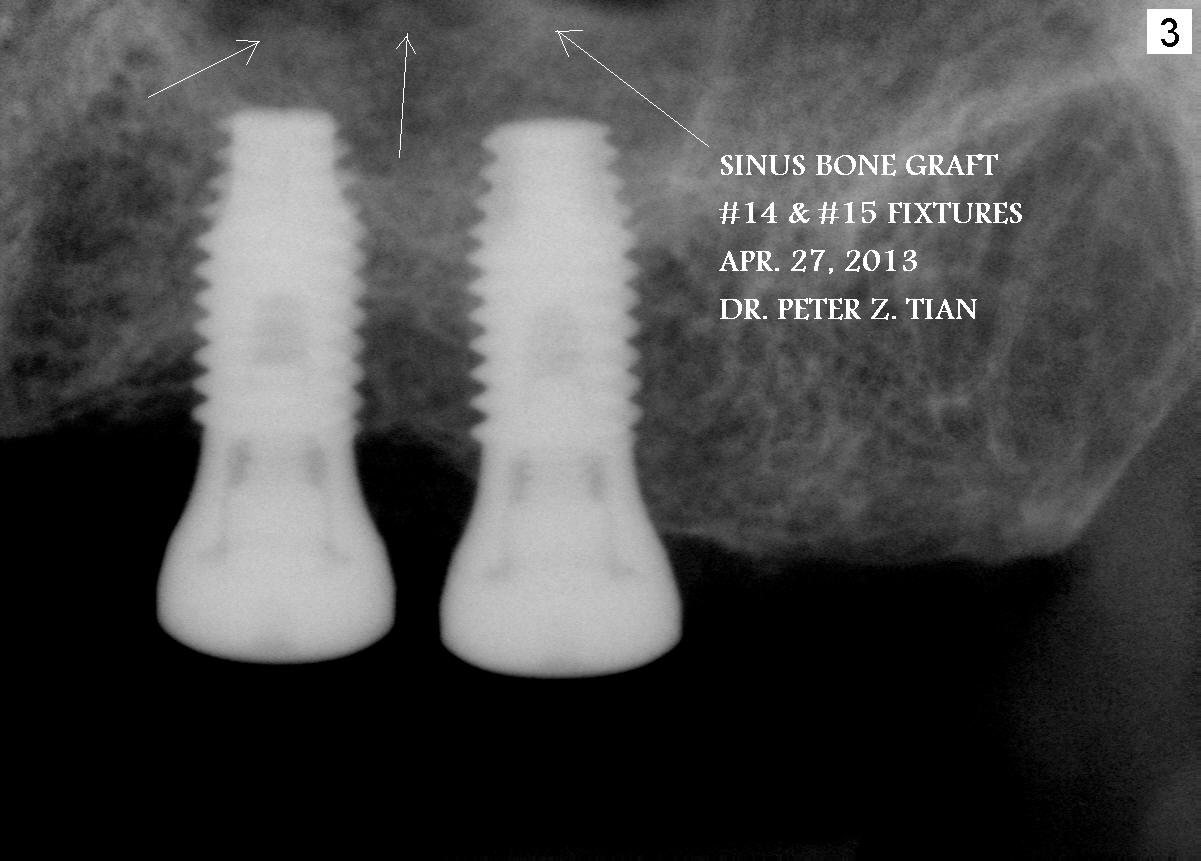

Peter: In fact, you open my eyes. How did you place these two implants so parallel? Used commercial surgical guide? Bone grafting looks terrific, although it is redundant to me. You must have spent time putting it into the sinus. Any leakage of graft into nasal cavity? It is fortunate to be your patients. What sizes of these implants? Xin Wednesday, May 1, 2013 10:22 PM

I used free hand drilling and I am very good about that. You need to training yourself. Basically, I need to watch the drill 3 angles, front, buccal and lingual to make sure they are parallel to #12 all the time.  I don't use commercial guide, it costs $$$.  I used little over 1g of bone. It took me about 1.5 h from sitting patient, to raise the flap, drill, lift, inject the bone, place implants, suture, give the instruction and collect the payment. No leaking, I used hydraulic sinus lift so that patient and I would know if there is any water leaking right away. Patient's son in law is ENT specialist. They know this very well.  Implants 4.8mm x 10mm, the bone thickness 7mm and 6mm. Peter Wednesday, May 1, 2013 10:36 PM

Dr. Wei, Please feel free to post them on your site.  Hydraulic sinus lift is a technique to lift sinus membrane by slow injecting normal saline water little by little and bone graft after crestal approach osteotomy. It is safer and predictable. Peter Thursday, May 2, 2013 1:19 PM